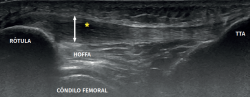

It is also common to identify cortical irregularities in the proximal enthesis of the tendon at the point where it joins the patella, involvement of the paratendon and adherences to Hoffa's fat pad. Any calcifications will be seen as white hyperechogenic zones (Figure 5).

The most common MRI finding is increased signal intensity in the lower pole of the patella, with local widening of the affected zone of the tendon (Figure 7)(14,25). The most evident advantage of MRI with respect to ultrasound is its capacity to visualise associated lesions in the joint and cartilage, as well as the presence of bone edema and involvement of Hoffa's fat pad (Figure 7). As clear disadvantages, mention must be made of the high cost of the technique and the impossibility of performing exploration in motion or at different angles of flexion of the knee.